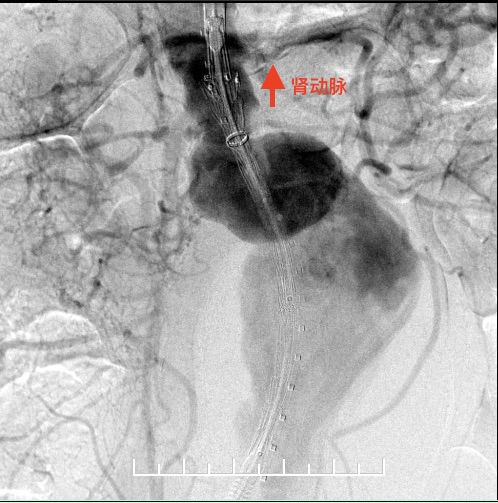

右肾动脉闭塞,精确定位左肾动脉开口释放支架。

左股动脉入路导丝超选短腿失败,经右侧肱动脉使用导丝穿针引线从股动脉引出。

左侧放置第一枚髂腿支架(16mm*140mm,美敦力)

左侧放置第二枚髂腿支架(16mm*140mm,美敦力)

右侧完全释放主体再接一枚16mm-14mm 髂腿支架于髂总动脉近段(美敦力)